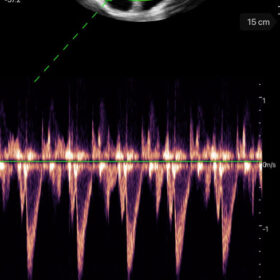

Mindray I3P WiFi Probe Image Gallery and Videos

Display mode: B, B/M, and Color, PW, PDI